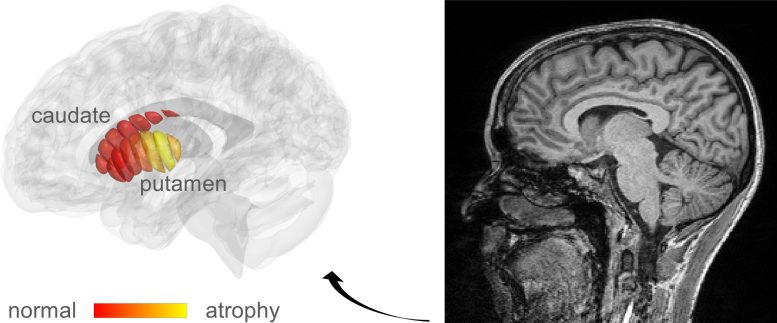

Researchers at the Hebrew University of Jerusalem (HU), under the direction of Professor Aviv Mezer, came to the conclusion that by modifying a related method known as quantitative MRI (qMRI), it could be possible to reveal the cellular changes in Parkinson’s. With the use of their technique, they were able to examine the microstructures of the striatum, an area of the deep brain that is known to degenerate as Parkinson’s disease progresses.

MRI Images Parkinson's

MRI images used for the automatic detection of microstructural changes in early-stage Parkinson’s Disease (PD) patients. Marked in yellow are areas in the putamen where PD patients show tissue damage, compared to healthy controls. Credit: Mezer Lab/Hebrew University

Using a new method of analysis, developed by Mezer’s doctoral student, Elior Drori, biological changes in the cellar tissue of the striatum were clearly revealed. Moreover, they were able to demonstrate that these changes were associated with the early stages of Parkinson’s and patients’ movement dysfunction. Their findings were recently published in the prestigious journal Science Advances.